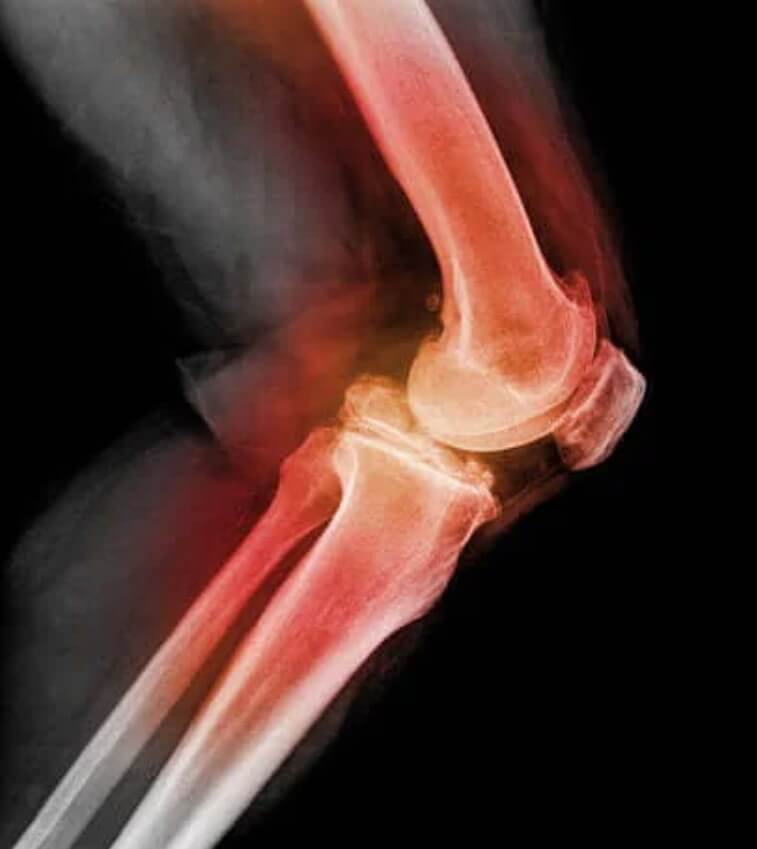

Για να διαγνώσει την εξάρθρωση επιγονατίδας ή του γονάτου, ο γιατρός θα αγγίξει την επιγονατίδα και θα λυγίσει το γόνατο, μετακινώντας την προς διαφορετικές κατευθύνσεις. Χρησιμοποιώντας ακτινογραφίες, μαγνητική τομογραφία (MRI) ή υπολογιστική τομογραφία (CT), μπορεί να δει εικόνες από το εξάρθρωση του γόνατος και άλλους τραυματισμούς στο γόνατο.